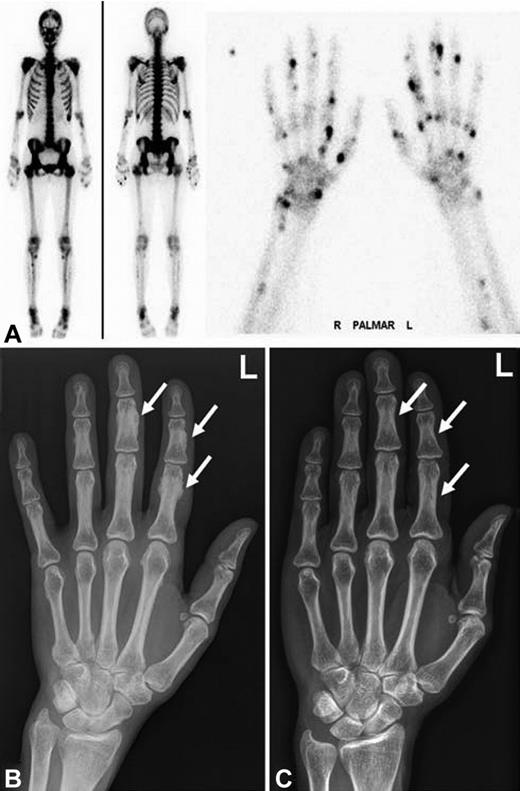

We report 3 patients on long-term voriconazole treatment who developed clinically significant skeletal disease, which was completely reversible after termination of voriconazole (Table 1). All 3 patients were female allogeneic stem cell transplant recipients with cyclosporine-related moderate chronic renal failure. Disseminated bone pain started between 3 and 7.5 months of voriconazole treatment. Laboratory findings included an elevated alkaline phosphatase and bone-specific alkaline phosphatase, normal levels of calcium, phosphate, parathyroid hormone, 25-hydroxyvitamin D, and a slightly elevated urinary deoxypyridinoline/creatinine quotient. Conventional radiographs, CT scans, and bone scintigraphy revealed periosteal appositions and focal tracer uptake, respectively (Figures 1 and 2). CT scans of the chest and abdomen showed no signs of secondary malignancies, and bone marrow biopsies ruled out recurrence of the acute leukemia. Patients 1 and 2 were initially misdiagnosed as having an unusual musculoskeletal presentation of GVHD; hence, the immunosuppression was intensified. However, the pain was only temporarily attenuated by corticosteroids and methotrexate but disappeared almost completely in all 3 patients within 4 days of voriconazole cessation. The diagnosis of voriconazole-induced skeletal disease was made only retrospectively in patient 1, 20 months after occurrence of the first symptoms in patient 2, and without delay in patient 3. Serum fluoride measurements at diagnosis were available for patients 2 and 3 with > 10-fold elevated levels and a marked decrease within 3 weeks of voriconazole cessation (81% and 57% of precessation values, respectively). Long-term follow up of 5.5 years after the initial diagnosis revealed complete resolution of the skeletal changes in patient 1 (Figure 1).

Radiographic findings and bone scintigraphy in patient 1. (A) Technetium 99m-methyl-diphosphonate bone scintigraphy showing marked tracer uptake in the entire skeleton, most pronounced in the spine and pelvis (left). There are multiple active spots in bones of both hands (right). (B) Plain film showing marked periosteal bone apposition on diaphysis of the phalanges of the left hand (arrows). Findings are typical for hypertrophic osteoarthropathy. The image was taken after 9 months of voriconazole therapy. (C) Plain film showing resolution of periosteal bone appositions on diaphysis of the phalanges (arrows). The image was taken 5 years after cessation of voriconazole therapy.